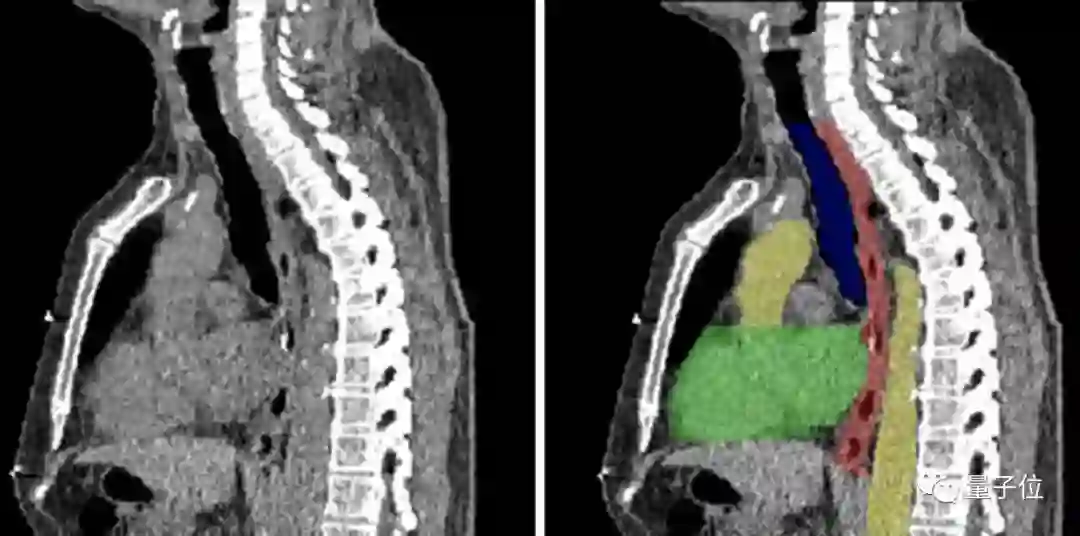

图像分割,顾名思义,就是将图像切分为多个区域,来简化或改变图像的表现形式,从而让图像变得更加容易解读和分析。

目前,图像分割技术用在了肿瘤和其他病理位置定位、组织体积测量、解剖学研究、计算机辅助手术、治疗方案制定以及临床辅助诊断等多个细分领域。

图像分割的实现方式也不难理解——以图像中的自然边界,例如物体轮廓、线条等,将图像切分为多个区域。

在计算机中,是对图像中的每个像素加上标签,并认为具有相同标签的像素有着某种共同视觉特性,从而来实现分割。

传统中有基于聚类、阈值、边缘、区域等特征的方法。但随着AI技术的发展,基于深度学习的方法效果出众,超过人类,成为最广泛的应用。

这其中,全卷积网络(Fully Convolutional Network, FCN)、U-net 和 V-net 是常见的几种基于深度学习的图像分割方法。

但在医疗领域中,应用最为广泛的则是U-net 。需要分割的图像有其独特性,大多数情况下是针对一个指定器官的成像,而非全身。

器官本身结构比较固定,语义信息并非特别丰富。

所以高级语义信息和低层级特征就显得重要,而 U-net 的 U 型结构和跳跃连接在这种场景中,可以发挥出更大作用。

近年来,U-net 在医学影像 分割领域良好的应用效果,已在很多部署中得到充分了证明。

良好的图像分割模型,能有效帮助医疗机构提高医学影像判读效率,进而增强临床诊疗能力、提升疾病治愈率以及减少病患等待时间,弥补因医疗机构影像科资源缺乏带来的多种问题。